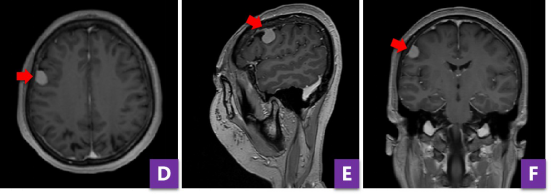

由于患者本身没有基础病,身体状态好,越早进行开颅术创伤越小,越有利于术后恢复。为此,神经外科团队制订了综合的手术方案。术前,为精准定位肿瘤位置,张培海使用神经导航辅助,借助计算机系统的红外追踪器分析CT与磁共振影像上的肿瘤信息,最终精准锚定肿瘤位置。同时借助导航系统,为患者“量身定制”了发际线内5cm的微创弧形切口,仅需剔除切口附近的头发,最大程度地降低患者身体和心理创伤。

张培海医师为病人导航,设计微创切口